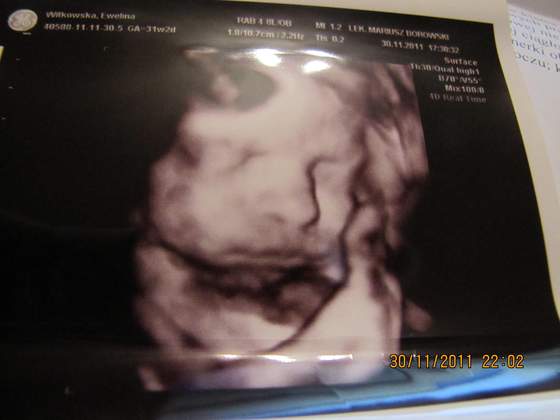

EwelinaK, super fotka malego... Sliczna buzia.